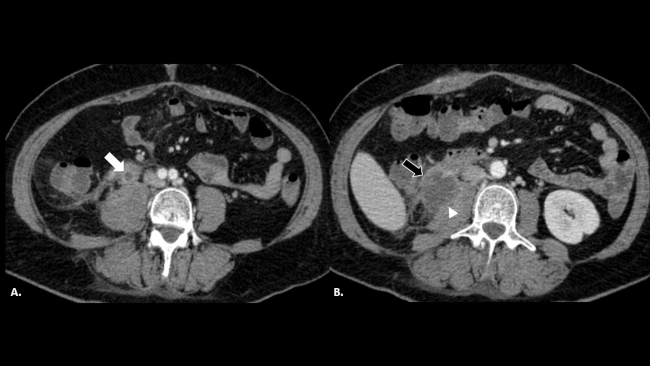

La TC con contraste endovenoso es por amplio margen la mejor técnica para el diagnóstico del EMU. Se trata de un estudio rápido, con alta sensibilidad y especificidad, que nos permite (►Fig. 2) no solo demostrar la existencia de un EMU visible como una estructura tubular dilatada en el trayecto del uréter remanente, con refuerzo y engrosamiento de su pared, sino que también nos ayuda a evaluar las posibles causas del mismo (litiasis, compresión extrínseca de la pared del muñón o tumores) y complicaciones como abscesos asociados en peritoneo o en músculo psoas (►Fig. 3).4,5,6,7,8

Paciente trasplantado renal. TC de pelvis con contraste endovenoso (a) en donde se reconoce colección con refuerzo de sus paredes (flecha blanca) adyacente al riñón trasplantado (cabeza de flecha). TC de abdomen del mismo paciente (b), evidenciándose dilatación e inflamación del muñón ureteral izquierdo remanente (flecha negra).

Es importante tener en cuenta que la sensibilidad y especificidad de la TC aumenta en un tomógrafo multislice en relación a un helicoidal, debido al menor espesor de corte y a las reconstrucciones multiplanares. Los hallazgos tomográficos característicos muestran una estructura tubular retroperitoneal dilatada, con refuerzo de sus paredes, en topografía del uréter remanente, con contenido líquido en su interior, en pacientes con el antecedente de nefrectomía homolateral. Una vez realizado el diagnóstico, es necesario evaluar las posibles causas de enfermedad, descartando litiasis, tumor o patología inflamatoria genitourinaria. Desde el punto de vista terapéutico, en la mayoría de los casos se realizará tratamiento antibiótico empírico con posible resolución quirúrgica en un segundo tiempo según su evolución.10,11,12 En algunos casos, se realizará tratamiento intervencionista con un drenaje percutáneo en pacientes con colecciones extraureterales asociadas (►Fig. 6).

TC de abdomen con contrate endovenoso donde se observa en (a) uréter remanente derecho dilatado, con cambios inflamatorios adyacentes (flecha blanca). (b) Colección organizada originada en el extremo caudal del uréter remanente (flecha negra), con afectación del músculo psoas homolateral (cabeza de flecha).